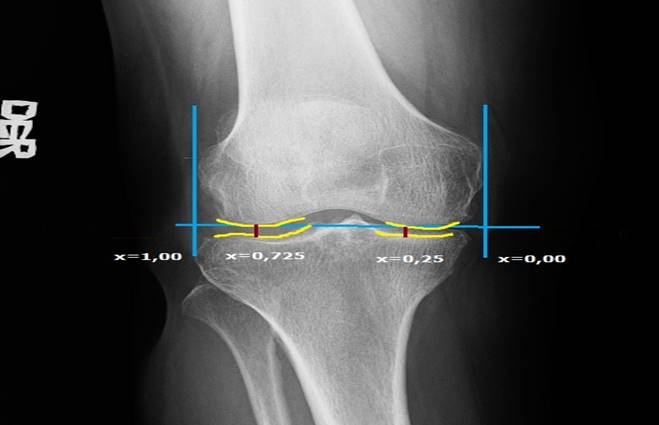

Por su parte en el método de superficie, se dibujan los contornos de los cóndilos femorales y los de la tibia proximal (amarillo), se traza una línea que une los dos cóndilos femorales y dos líneas que interceptan esta última en 90 grados, se tienen como referencia los puntos más externos de los cóndilos medial y lateral (azul). Luego, se identifican de esta línea el punto 0,25 y 0,725 donde se trazan dos líneas (rojas) verticales paralelas a las azules de los cóndilos y se realiza la medición del espacio tibiofemoral (Figura 3). 26